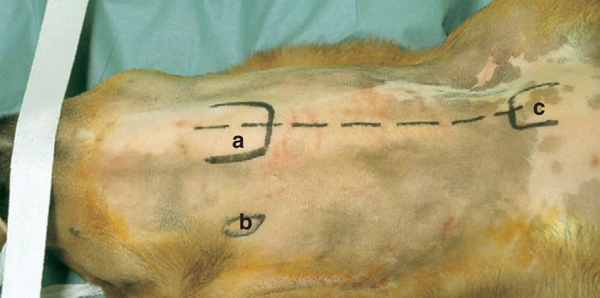

Những mốc giải phẫu quan trọng cần xác định trước khi phẫu thuật bao gồm:

a) Cổ họng – nằm ở mặt trước cổ, cần tránh tổn thương trong quá trình tiếp cận.

b) Cánh ngang của cột sống trục – đóng vai trò là điểm mốc giúp xác định vị trí đốt sống.

c) Tay cầm xương ngực – là điểm tham chiếu giúp định hướng trong quá trình phẫu thuật.

Ngoài ra, mạch da chạy theo đường trung tâm của cổ, thường được biểu thị bằng đường chấm trong hình ảnh giải phẫu, giúp định vị và tránh tổn thương khi rạch da và bóc tách mô.